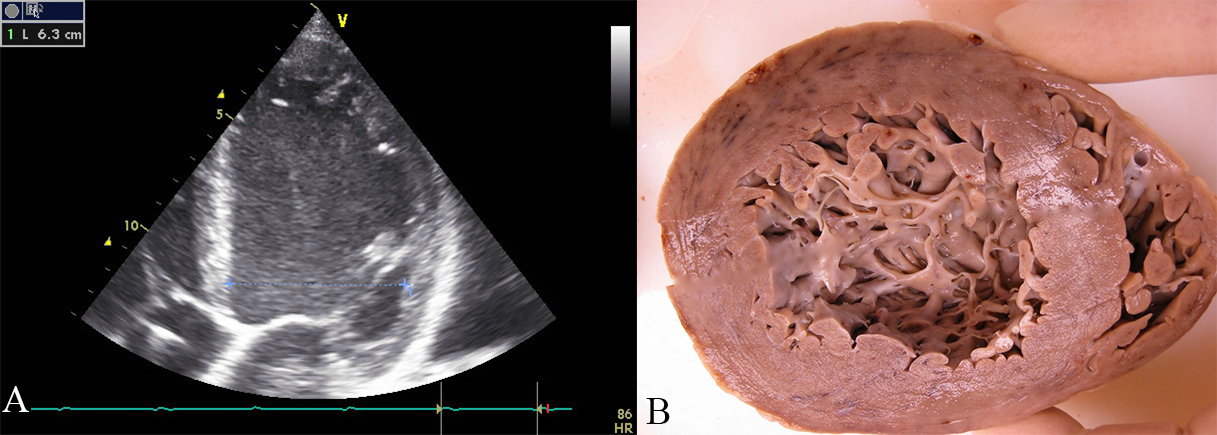

The human left ventricle has a smooth endocardial surface. Anatomic inspection of the inside of the left normal ventricle discloses papillary muscles and — occasionally — false tendons and aberrant bands — and up to three prominent left ventricular trabeculations are found [9]. In rare cases, more than three trabeculations with intertrabecular recesses are found in the left ventricle (Fig. 1A) [10]. Different names, such as “left ventricular hypertrabeculation”, “noncompaction” or “persisting sinusoids” are used for this abnormality. We prefer the purely descriptive term LVHT.

Fig. 1.Echocardiographic and pathoanatomic picture of left ventricular hypertrabeculation/noncompaction. (A) Echocardiographic apical four-chamber-view of a patient with dilated cardiomyopathy. Four trabeculations are visible in the apex of the left ventricle, thus fulfilling the criteria of Stöllberger et al. [10] for left ventricular hypertrabeculation/noncompaction. (B) One week after echocardiography, the patient died due to heart failure. The formaldehyde-fixed heart is opened along the short axis. A heavily trabeculated apical portion of the left ventricle is visible.

Transthoracic echocardiography is the most frequently applied method for diagnosing LVHT because it is non-invasive, without radiation, needs usually no contrast medium, widely available and unexpensive. Echocardiography, on the other side, has disadvantages because it is highly dependent on the experience of the investigator. The image quality may be impeded, especially in the apical region, where LVHT is frequently located (Fig. 1B). Thus, by echocardiography, LVHT may be over- as well as under-diagnosed [4]. Currently, different echocardiographic criteria are used and their application may influence the prevalence of LVHT (Table 1, Ref. [2, 11, 12]). A further problem in diagnosing LVHT by echocardiography is the poor inter- and intra-observer agreement, especially when investigators from different laboratories are compared [13].